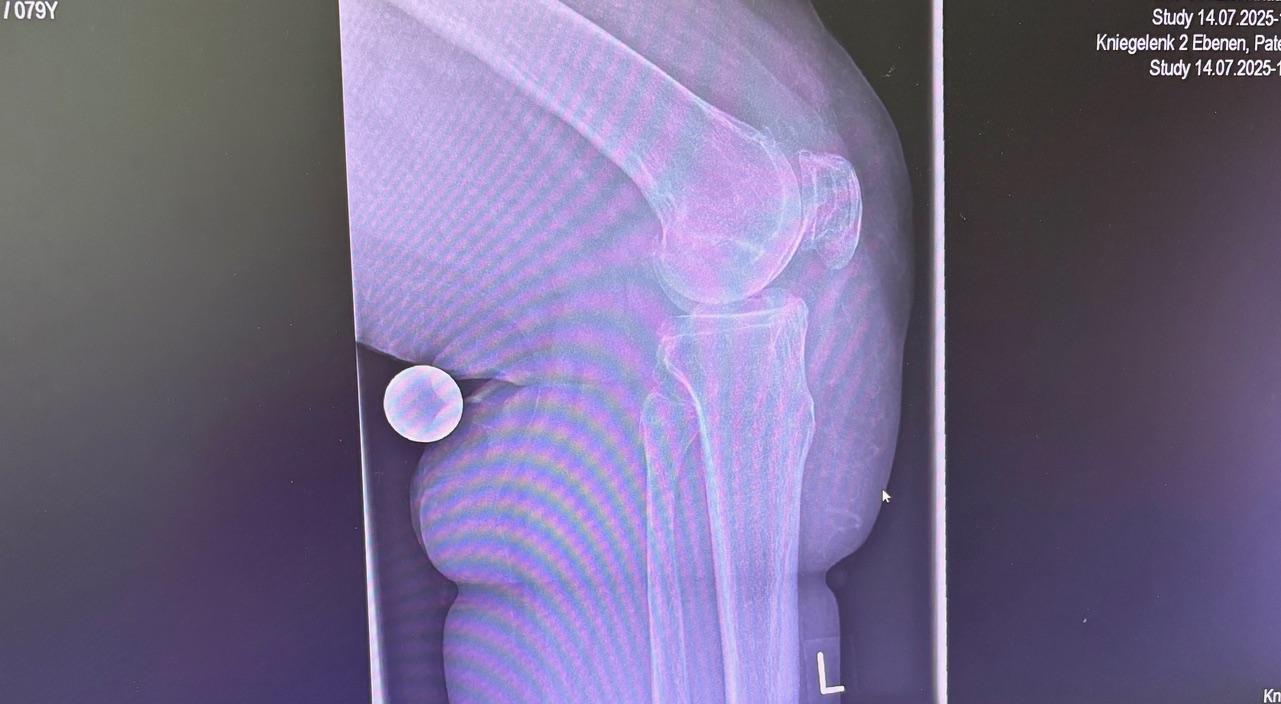

- Προεγχειρητικός σχεδιασμός με CT (συνήθως) → 3D μοντέλο γόνατος

- Καθορισμός ακριβών ορίων κοπών και ευθυγράμμισης

Πότε ενδείκνυται

- Προχωρημένη οστεοαρθρίτιδα γόνατος

- Παραμορφώσεις (ραιβό / βλαισό γόνατο)